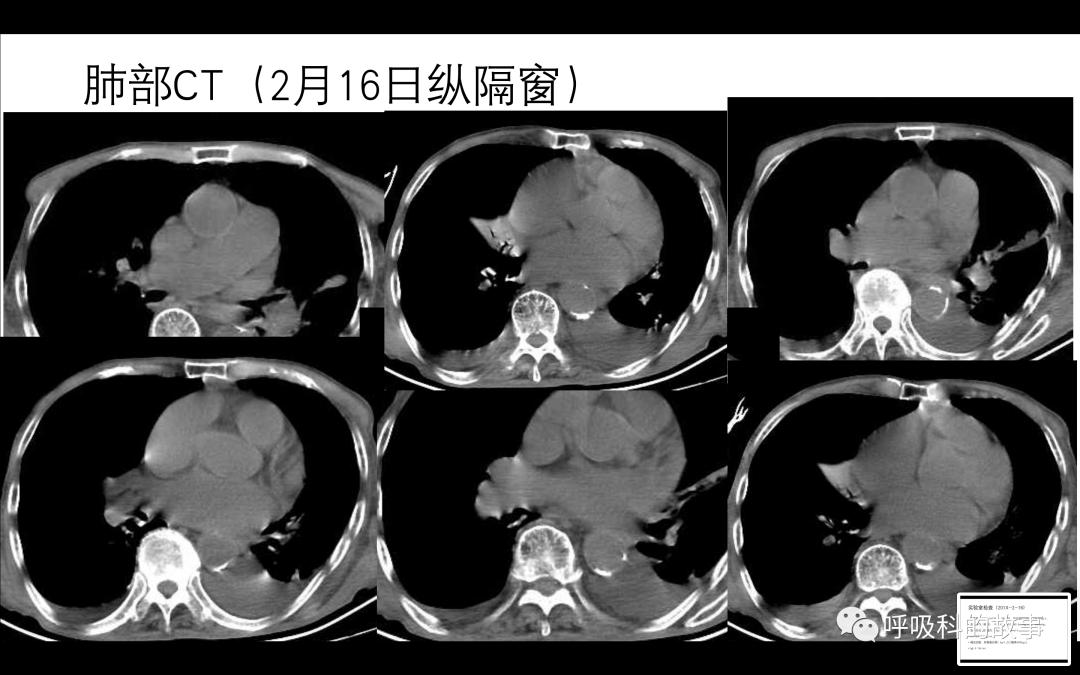

肺部影像结果如下:

2-26肺部CT检查,可以看到和入院时的CT大致相当,并没有大片渗出和实变改变:

关于痰培养曲霉的问题,同样要仔细思考。患者高龄且有慢阻肺病史,合并曲霉感染的风险较高,但并不意味着痰培养出曲霉就一定有曲霉感染。从影像上看,肺部既没有坏死空洞样改变,也没有粘液栓和树芽征等表现。血嗜酸细胞和IgE不高,也提示没有曲霉致敏的情况,那么这个时候也可以不需要抗曲霉治疗。